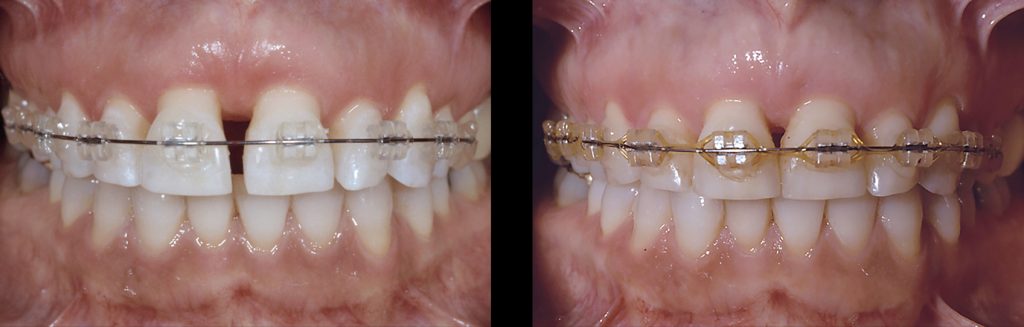

Provisionals: Yes

Splinting provisionals offers numerous benefits. It enhances the strength and retention of the provisionals, making fabrication easier. The only time I wouldn’t splint provisionals is before orthodontics, where the teeth need to be able to move independently. When restoring an arch of teeth, it is typically easier to keep the provisionals in three segments (an anterior segment — cuspid-to-cuspid — and two posterior segments).